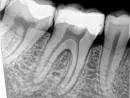

Подскажите, пожалуйста, что бы вы посоветовали в сложившейся ситуации, насколько мой случай запущен? Прилагаю фото зуба.

Прикрепленые фото